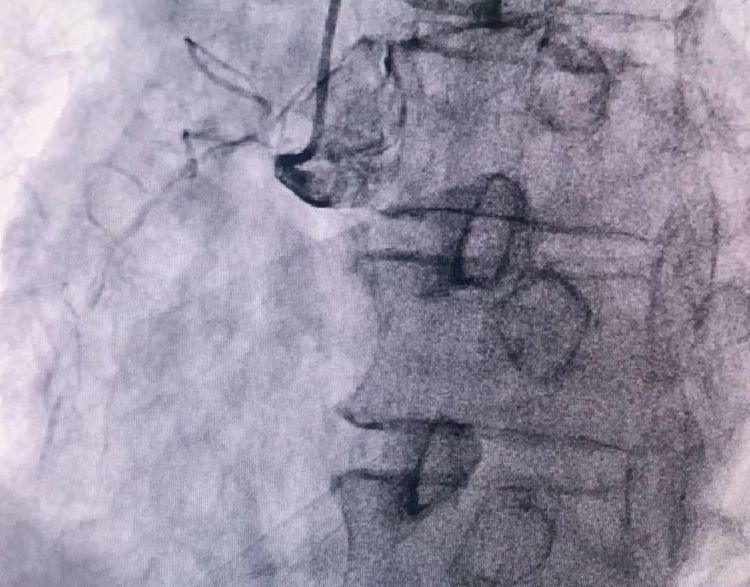

患者前降支、右冠100%閉塞,LCX中段60%狹窄。命懸一線,手術(shù)臺(tái)上持續(xù)胸痛。和患者家屬及時(shí)溝通后,決定行PTCA術(shù)。血壓低至60/40mmHg,在主動(dòng)脈內(nèi)球囊反博的支持下緊急行PCI術(shù)。軌道很快建立,導(dǎo)絲也及時(shí)通過(guò)病變血管,噩夢(mèng)來(lái)了,患者發(fā)生室顫了。在吳棟梁院長(zhǎng)的指揮下,李陽(yáng)主任和心臟團(tuán)隊(duì)的成員共同努力下,除顫、冠脈內(nèi)溶栓、多個(gè)球囊輪流上陣,患者病情平穩(wěn)了,罪犯血管及時(shí)開(kāi)通,血流恢復(fù)三級(jí)血流。平安下臺(tái),準(zhǔn)備擇日再處理冠脈情況。